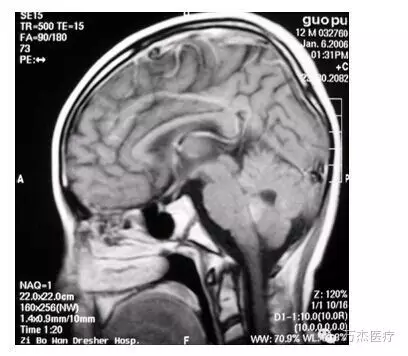

典型病例(髓母细胞瘤):

治疗前